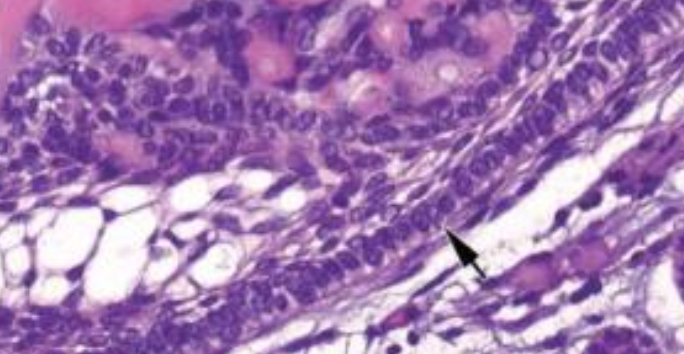

| Branchial Cleft Cyst (cervical lymphoepithelial cyst,鰓裂囊) |

branchial arches 殘留 (2nd,95%) | SCM 前/下 |

10 - 40y | 複層鱗狀、淋巴、發中心(germinal center)。 |